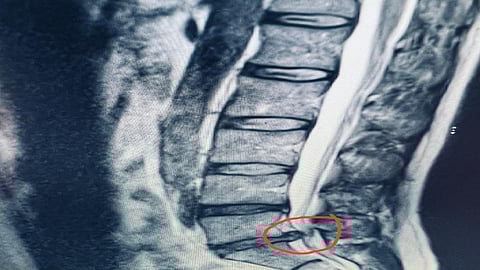

وبفحص المريض ومناظرة أشعة الرنين المغناطيسي تبيّن وجود انزلاق غضروفي كبير تسبب في ضغط على العصب الطرفي بين الفقرة القطنية الخامسة والعجزية الأولى.

وأجريت عملية للمريض باستخدام الميكروسكوب أزال خلالها الغضروف المتسبب في الضغط على العصب إزالة كاملة وتم توسيع مسار العصب الطرفي، وتماثل المريض للشفاء مع اختفاء الأعراض التي كان يشكو منها.